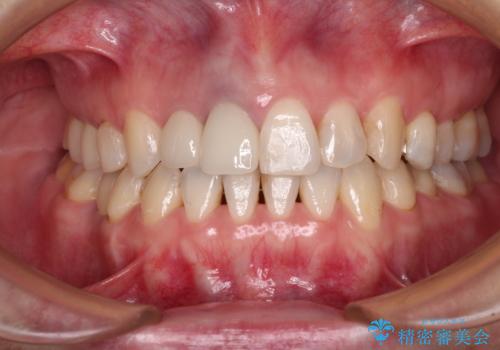

つぎはぎとグレーに透ける色が気になる 前歯のオールセラミッククラウン治療

- つぎはぎのある前歯のセラミックの色合いが気になるとのことで来院された患者様です。

グレーの色が透けて見える気がする点が気になっていらっしゃり、やや黄色みのある色を希望されていました。

仮歯に置き換えた後にオールセラミッククラウンにて補綴治療を行うこととしました。

統一感のあるきれいな色調となり、患者様には大変満足していただきました。